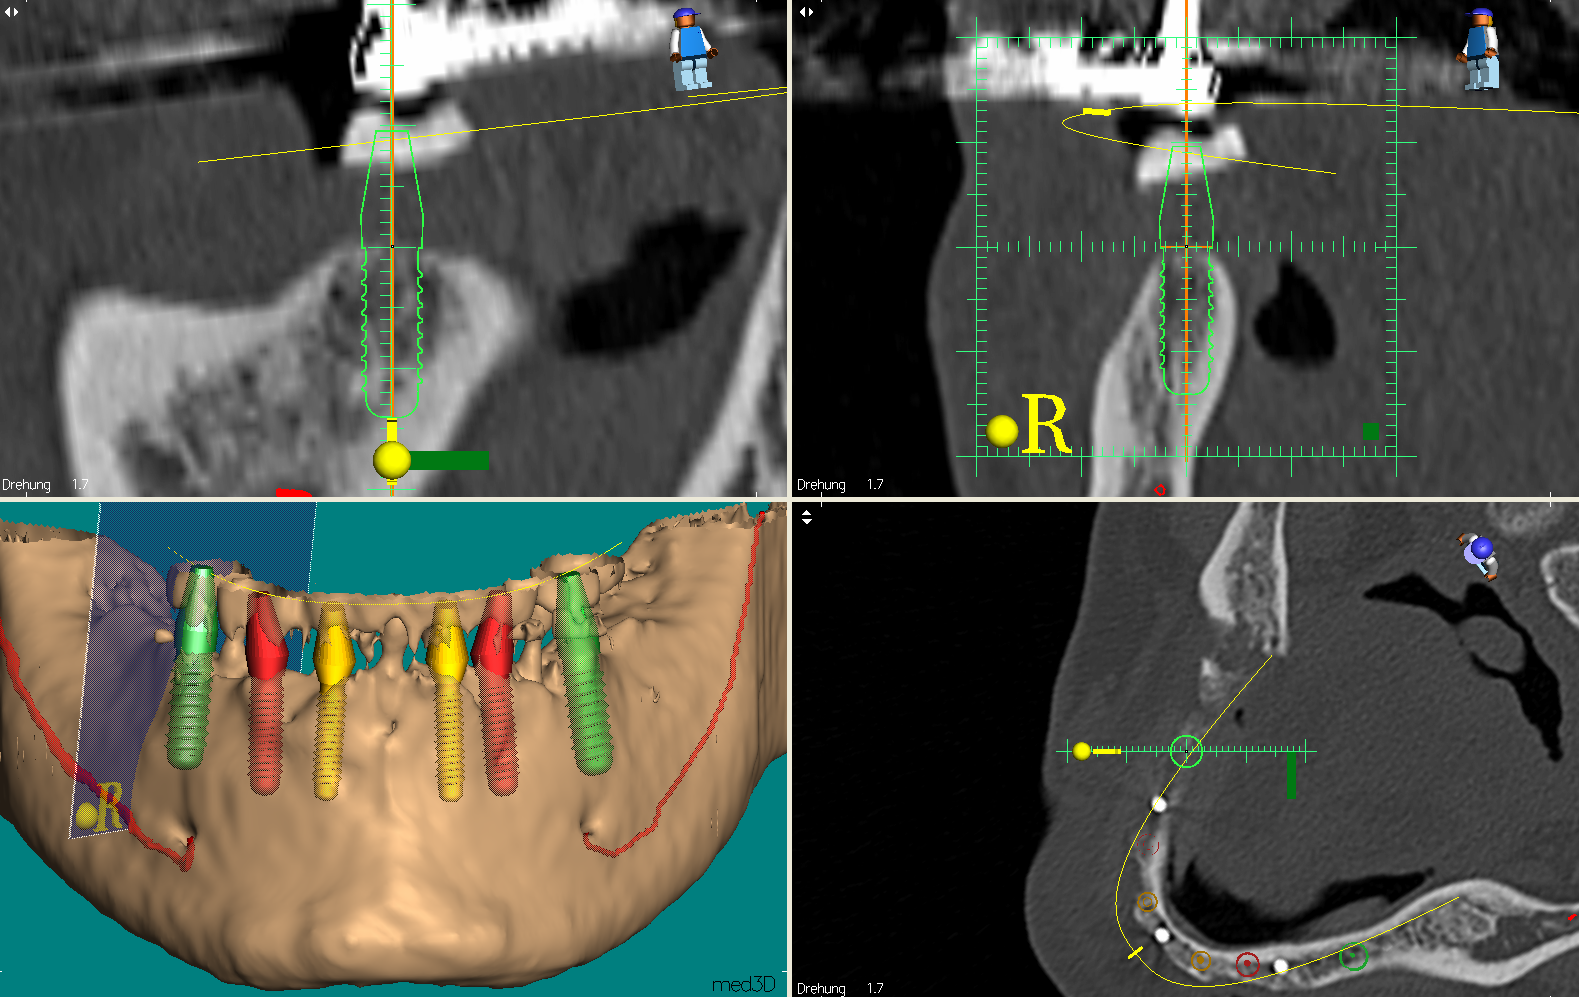

3D Implantatplanung und 3D optimierte Einbringung

Moderne bildgebende dreidimensionale Computer-Diagnostik ermöglicht mit speziellen Planungsprogrammen eine perfekte Implantatplanung individuell virtuell zu konstruieren. Dabei kann der vorhandene Knochen optimal ausgenutzt werden, da die 3D Aufnahme den Knochen im Zehntelmillimeterbereich wiedergibt, und dies in allen drei Dimensionen.